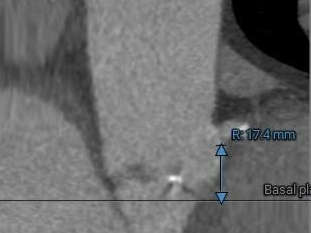

主动脉根部测量:

三叶式主动脉瓣,瓣叶增厚,R-N疑似钙化粘连,LVOT近似直筒型,非横位心。

•瓣环水平夹角约52°,非横位心 ,主动脉弓宽度、角度尚可,弓顶部有明显附壁钙化。